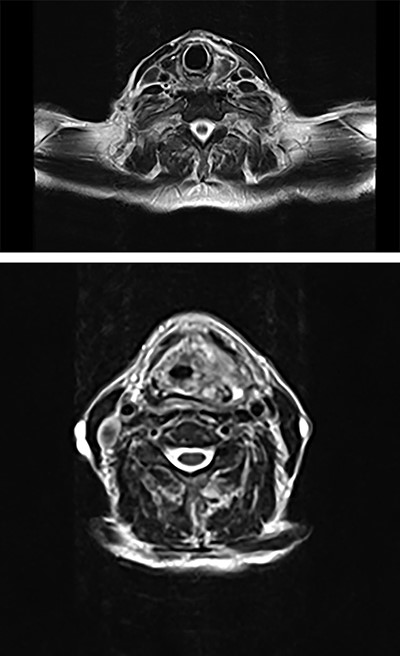

Intravenous Meropenem, Metronidazole and Fluconazole were continued, and he remained nil by mouth with nasogastric tube feeding. Water-soluble contrast swallow was undertaken after repeat CT showed emphysema progression (Fig. 3). A left sided oropharyngeal perforation was suggested.

Axial planes CT neck and thorax showing left parapharyngeal abscess with tracking into the prevertebral space, significant progression of air pockets in mediastinal and cervical soft tissue extending to right axillary region.